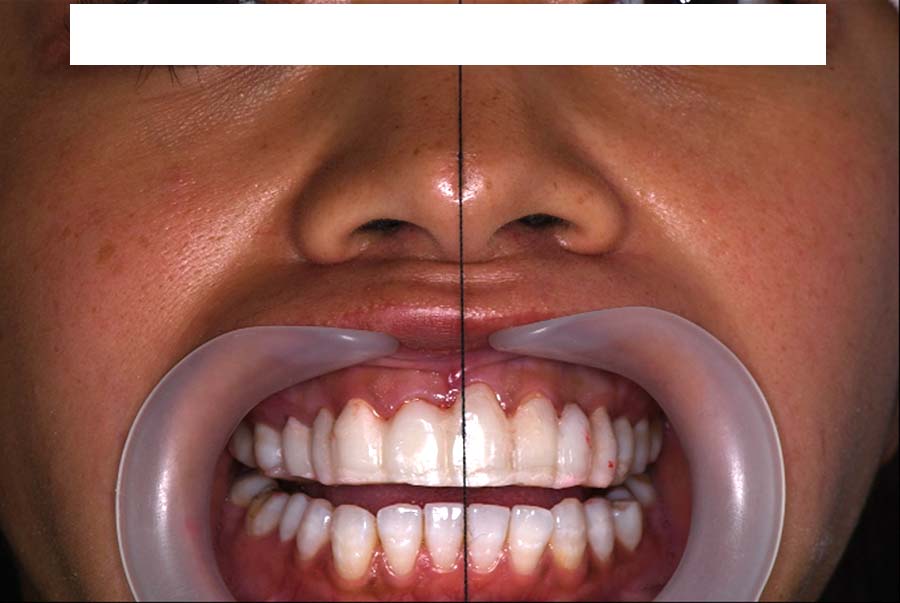

顔貌の変化

2024年 3月 初診時

2024年 10月10日

2025年 12月25日